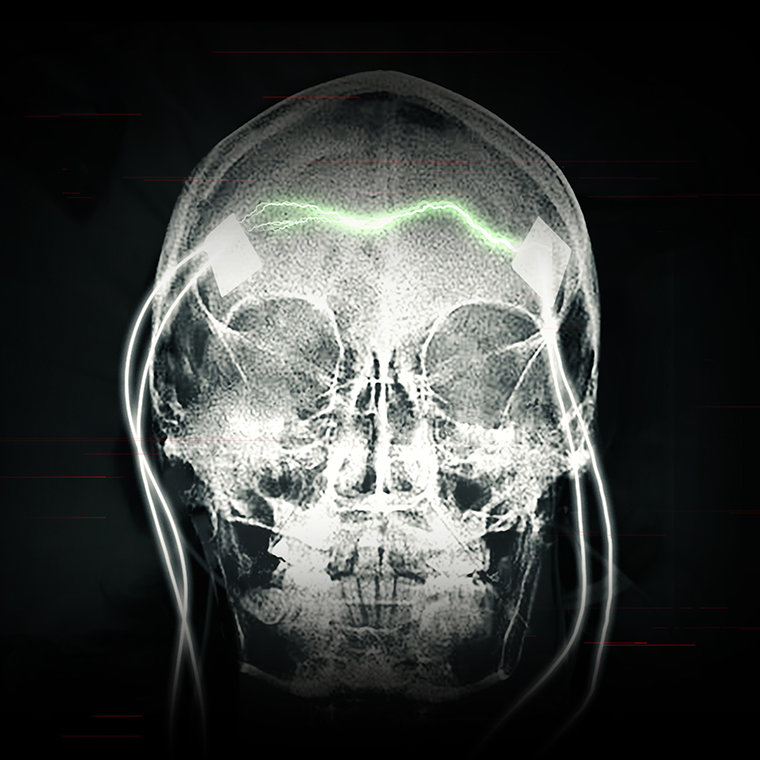

התוצאה נשארת בעינה: פרכוס גרנד מל ונזק מוחי, שיכול להיות תמידי. זרימת החשמל המוגברת היום במידה עצומה יכולה לקרוע חורים בתאי מוח ולהרוג את התאים. החשמל גם יכול להרוג את התאים על-ידי יצירת חום. בדיקות MRI שנעשו על מטופלים של ECT הראו צלקות וכיווץ של המוח – ראָיה חד-משמעית לנזק חמור.